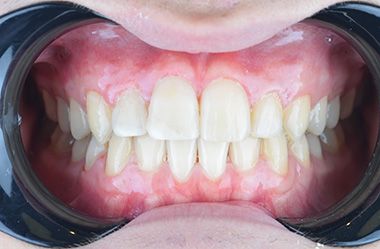

Firstly, we treated the gap between the teeth with Invisalign. We also corrected the angle of the front teeth. Invisalign Lite was enough. Glenn visited Turkey 4 times in a period of 8 months. During his last visit, we replaced the old fillings in his front teeth with composite bonding. We performed lingual retrainer to maintain the alignment of the teeth. We produced an sx plate for him to use at night and delivered it to him. Glenn was very happy. He said he wanted to study at a dentistry faculty.